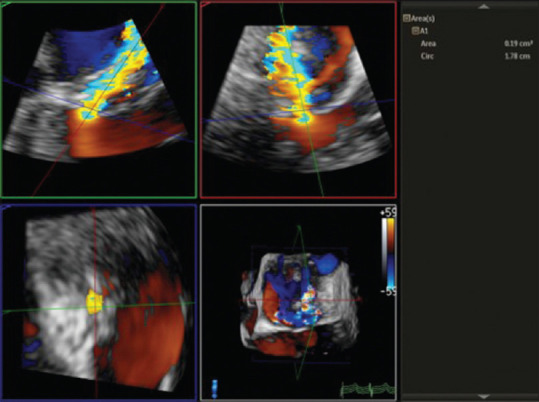

Background and aims: Intraoperative quantification of mitral regurgitation (MR) is sometimes necessary to quantify the severity of incidentally detected MR during cardiac surgeries. We aimed to compare and correlate the regurgitant volume (Rvol) and regurgitant fraction (RF) using 2D proximal isovelocity surface area (PISA) and 3D vena contracta area (VCA) with the 3D volumetric method and the integrated multiparametric approach.

Methods and materials: A prospective observational study was conducted on 37 patients undergoing mitral valve surgery for MR. Intraoperative quantification of the severity of MR was done using 2D PISA and 3D VCA methods and was compared with the 3D volumetric method. All three methods were compared with the integrated multiparametric method to obtain cutoff values for identifying severe MR.